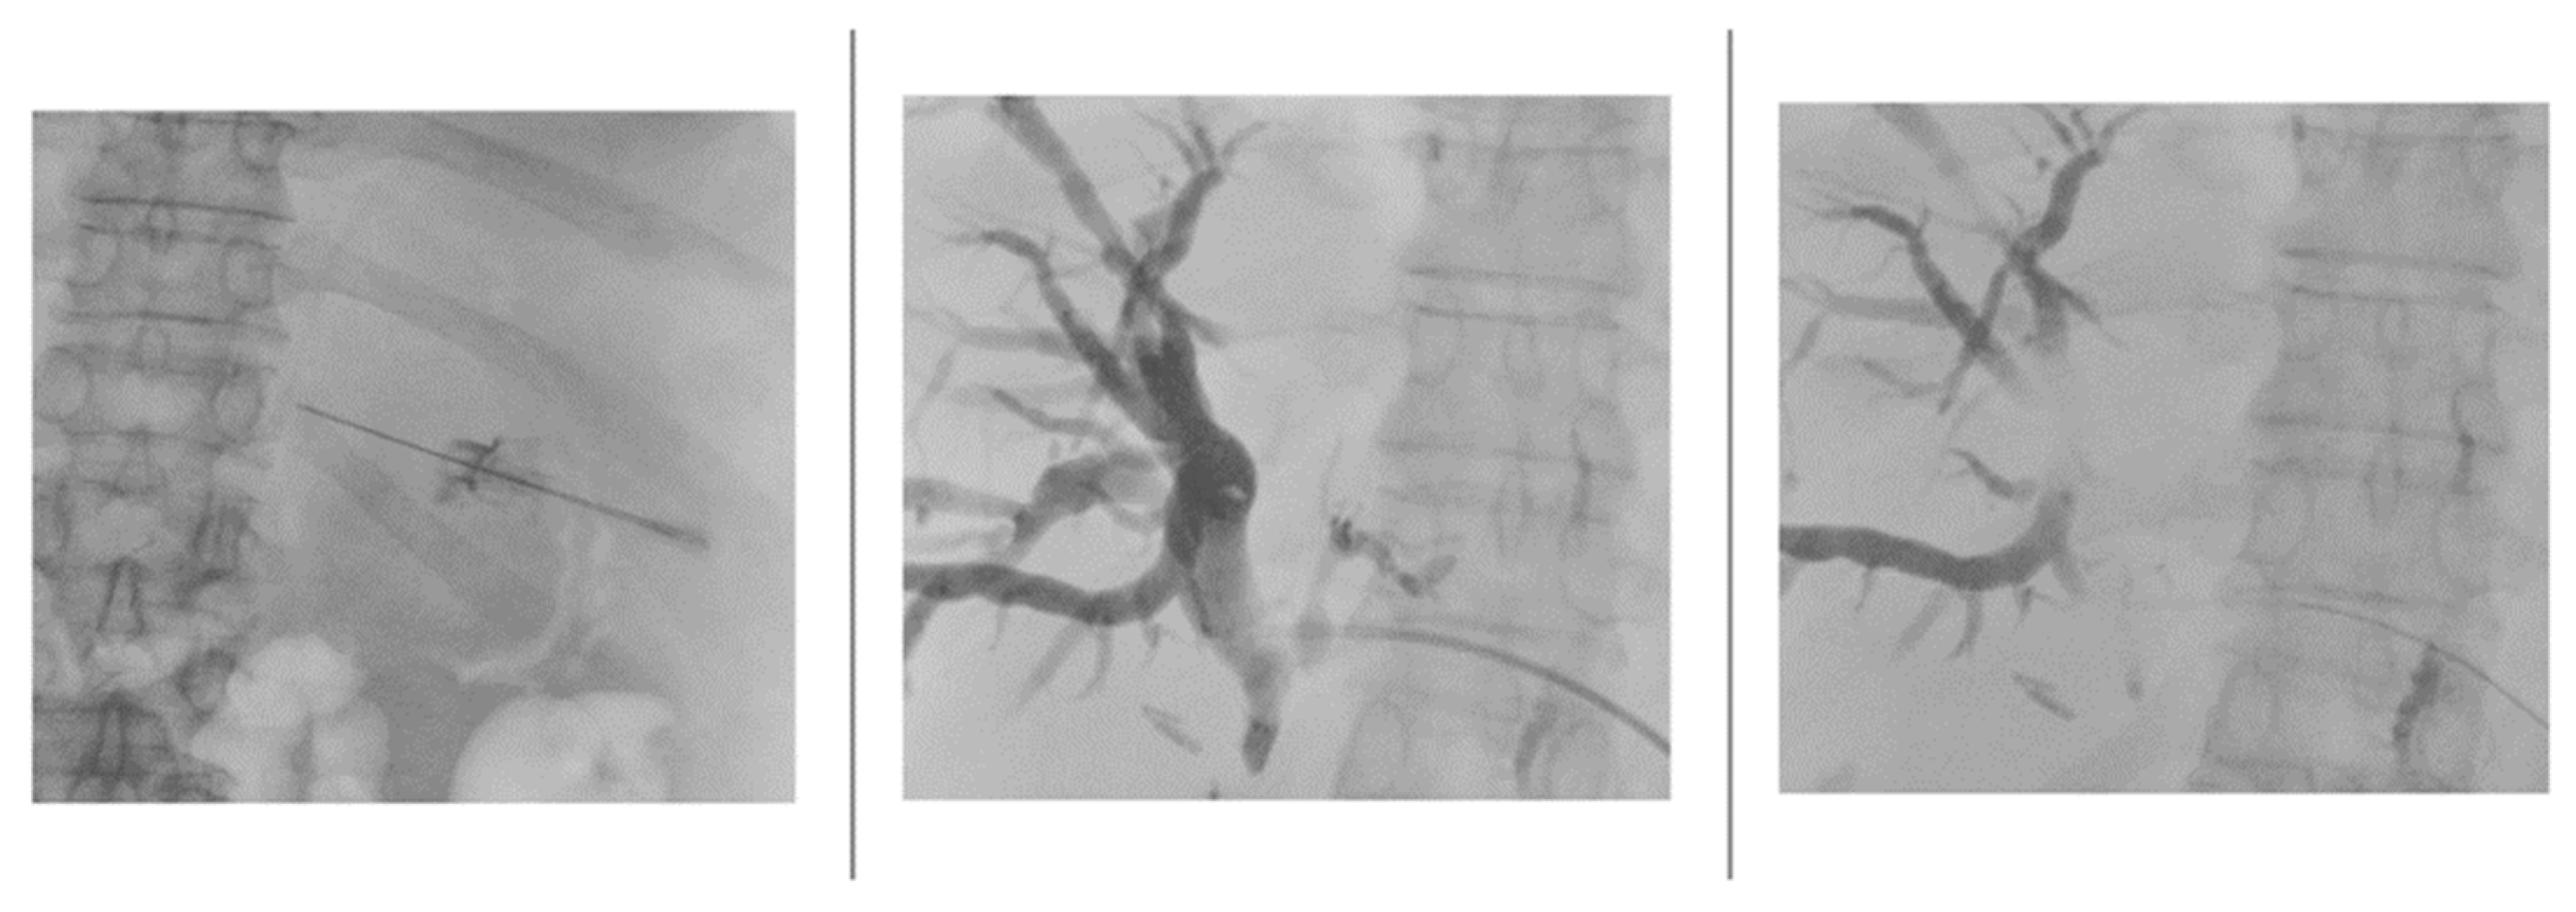

Once the lumen of the bile duct was penetrated and the needle stylet removed, the needle was disconnected from the needle guidance system to stably inject an iodinated contrast agent (Xenetix 250, Guerbet) mixed in a 1:1 ratio with saline to opacify the biliary tree under fluoroscopy guidance (Figure 3).

Figure 3. Images highlighting key moments of the cholangiography procedure, from needle insertion and visualization of the bile ducts to opacification and drainage placement.